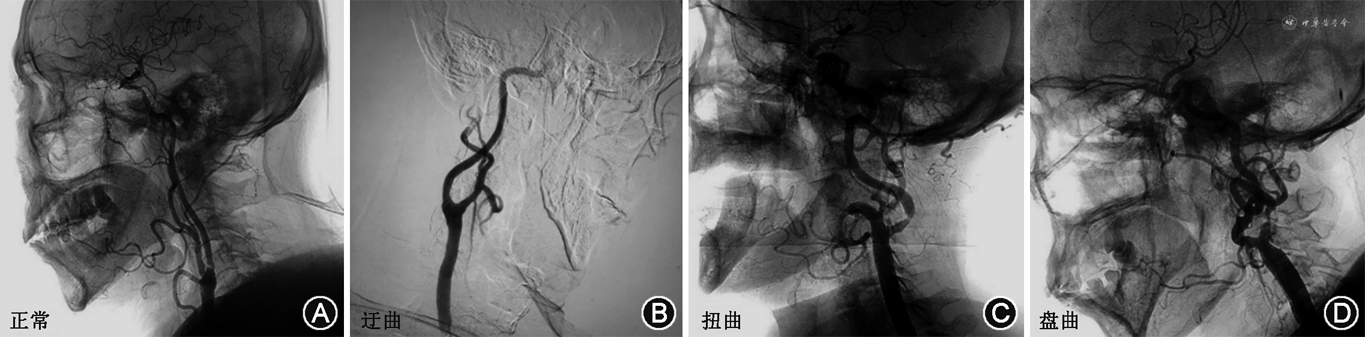

2. 颈动脉DSA相关数据获取方法:在DSA室无菌操作台下进行。局部麻醉后,穿刺股动脉或者桡动脉,先行主动脉弓上血管造影。随后导管分别超选入左、右侧颈动脉,行颈动脉3D造影。影像数据保存在CT工作站,经图像测量获得所需参数。(1)按颈动脉分叉位置对应颈椎水平:分为C2、C2~C3、C3、C3~C4、C4、C4~C5、C5(图1);(2)测量颈长:下颌角到锁骨中点的垂直距离定义为颈长(图2);(3)颈内动脉形态定义与分类:参考Weibel和Fields[3]的颈内动脉颈段走形异常分类标准,即根据扭曲程度分为3类:迂曲:指颈动脉非线性延伸成钝角;扭曲:指颈动脉扭曲成1个或多个锐角;盘曲:指颈动脉以横轴盘绕成1个袢(图3);该分类方法简便易行,能直观反映扭曲的严重程度。本研究根据颈内动脉扭曲程度,将颈内动脉形态分为颈内动脉扭曲组(包括颈内动脉扭曲和盘曲)和颈内动脉非扭曲组(包括颈内动脉正常和迂曲)。

3.颈内动脉形态类型分析:只要有一侧颈动脉扭曲或盘曲,即归入扭曲组。右侧颈内动脉非扭曲组(正常+迂曲)占84.8%(106/125),左侧占84.7%(127/150)。右侧颈内动脉扭曲组(扭曲+盘曲)占15.2%(19/125),左侧占15.3%(23/150)。女性患者中,颈内动脉扭曲占28.1%(9/32),男性患者中,颈内动脉扭曲占15.6%(24/154),不同性别间颈内动脉扭曲发生率差异无统计学意义(χ²=2.86,P=0.091)。高分叉组右侧颈动脉扭曲发生率为59.3%(16/27),高于非高分叉组的3.1%(3/98)(χ²=51.87,P<0.001);高分叉组左侧颈动脉扭曲发生率为30.4%(21/69),高于非高分叉组的2.5%(2/81)(χ²=22.45,P<0.001)。因此,高分叉组患者颈内动脉更容易发生扭曲。

除了颈动脉分叉高度,颅外段颈内动脉的形态学表现也与手术方式的选择息息相关。现有研究尚未明确颈动脉分叉高度与颈内动脉形态变异的关系。本研究首次发现,高分叉组颈动脉扭曲发生率:右侧59.3%,左侧30.4%,均远高于非高分叉组(右侧3.1%,左侧2.5%)。颈动脉分叉位置越高,颈内动脉形态变异的发生率越高。

对于颈动脉严重扭曲(例如盘曲)的患者,建议首选CEA。一是因为扭曲的血管使介入操作困难,远端脑保护装置通过困难、定位受限,支架无足够锚定区,并可能诱发操作后程血管痉挛;二是CAS不能去除冗长的动脉,并可能加重或造成新的扭曲。研究表明,严重扭曲的颈内动脉常伴有血管内皮功能受损,切除扭曲段的颈动脉能够更好地预防脑卒中[13]。对于颈动脉扭曲行CEA的患者,笔者建议手术时行外翻式CEA+颈内动脉扭曲矫正,而不是补片式CEA。若强行采取补片式CEA,由于补片较自体血管偏硬,将持续对远端颈动脉施加径向力,使吻合部位打折、迂曲,导致补片远端的狭窄[14]。对于颈动脉扭曲但因各种原因需行CAS的患者,笔者建议用近端脑保护装置来代替远端脑保护装置[15]。